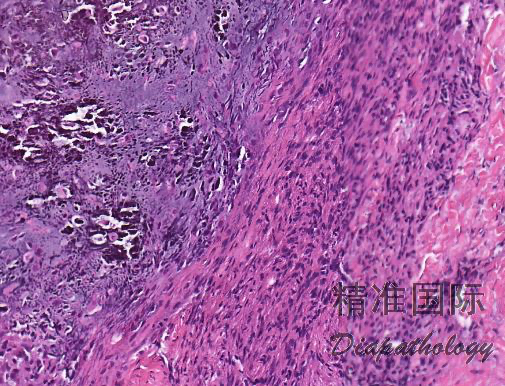

- 由胖梭形细胞栅栏状围绕软骨或点状钙化灶周围为其特征性改变;部分病例表现为梭形纤维母细胞浸 润性生长,细胞之间可见丰富的胶原纤维,两种结构可同时存在;

- 可浸润至周围的脂肪或横纹肌组织,或包绕血管和神经;

- 在钙化灶周围有时可见散在的破骨样多核巨细胞。